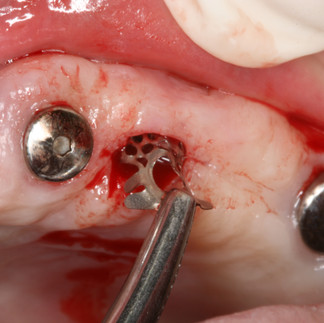

The CTi-mem (B1) was contoured and secured to the implant at the surgical site.

Primary closure was achieved with suturing to prevent exposure of the CTi-mem.